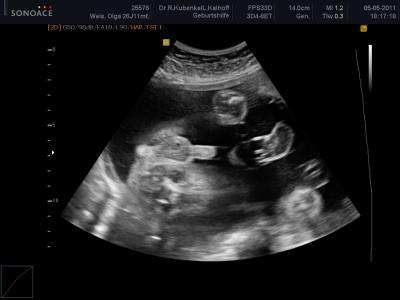

Hallo Ihr Lieben, möchte mich auch mal melden. Ich bin eine stille Leserin, aber ich lese und fiebere immer mit und drücke allen Mamis die Daumen. Heute war mein Mann wieder mit und nach 2 Std. warten könnten wir endlich rein. Es war wie immer super, dem Kleinen gehts gut (haben übrigens nochmal das Beweisfoto gekriegt versuche reinzustellen.) Er wiegt ca. 1100 gr. bei 26+5 SSW. Wir sind echt glücklich und erleichtert, dass alles in Ordnung ist. Liebe Grüße Olga mit Sophia+Sohnemann

Bild zu Zurück vom FA - Forum für August - Mamis